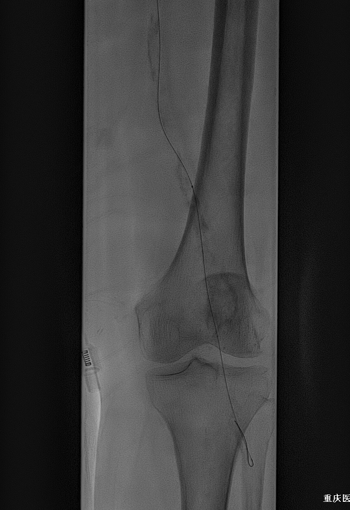

★ 病例介绍

男,81岁;

左足第4、5足趾溃疡2+周

既往:糖尿病病史30年;

ABI:L:0.57;R:0.19

★ 手术过程

图:术中

★ 手术结果

图:手术结果